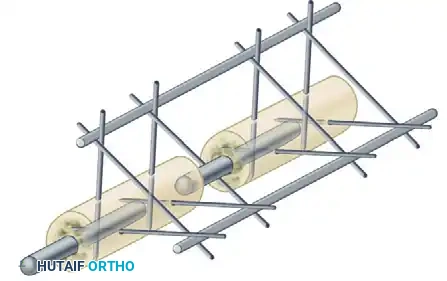

The rigidity of an external fixator construct is determined by several modifiable variables:

* Number of Bars: Adding a second longitudinal bar (creating a stacked or double-bar construct) significantly increases stiffness, particularly in bending and torsion.

* Multiplanar Constructs: Placing pins in different planes (e.g., a delta frame or biplanar construct) dramatically increases torsional and bending rigidity compared to a uniplanar frame.